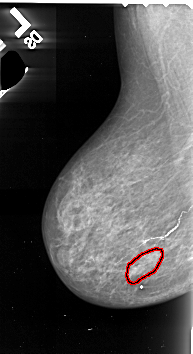

FILE: A_1071_1.LEFT_MLO.OVERLAY

TOTAL_ABNORMALITIES 1

ABNORMALITY 1

LESION_TYPE CALCIFICATION TYPE PLEOMORPHIC DISTRIBUTION SEGMENTAL

ASSESSMENT 4

SUBTLETY 2

PATHOLOGY MALIGNANT

TOTAL_OUTLINES 1

BOUNDARY